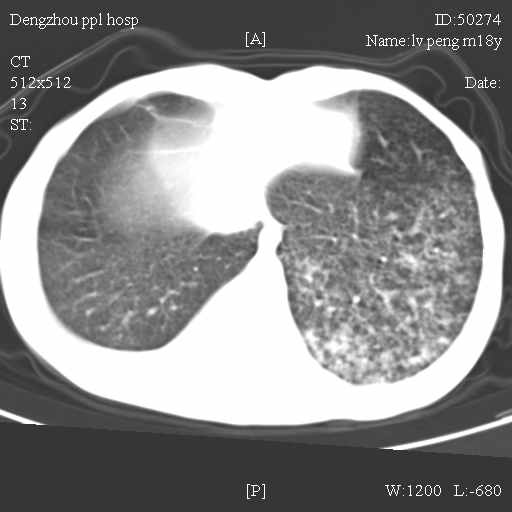

标题: CT10510:男.18岁,咳嗽咳痰两月.(有病理) [打印本页]

标题: CT10510:男.18岁,咳嗽咳痰两月.(有病理)

双肺布满大片状实变及网格状结节影,内参杂大小不等的气囊及空气支气管征,心脏增大。考虑:1 全身结缔组织疾病—系统性红斑狼仓?2 肺泡蛋白沉积症合并感染!

双肺布满大片状实变及网格状结节影,内参杂大小不等的气囊及空气支气管征,双侧胸膜腔少量积液,双下肺近膈面透亮度尚可,病人较年轻,病变较重(不知为什么上胃管?)考虑:1.胶原病肺部改变,2.组织细胞病x。结合实验室检查。

首先考虑组织细胞x病。两肺中上肺野多发囊腔,中下肺野内见多发小结节,并可见肺间质增厚。患者是男性,年龄较小。胶原性病变比较多见的类风湿、系统性红斑狼疮和硬皮病临床和影像均不是很支持,类风湿和系统性红斑狼疮的肺部表现最常见的是胸腔积液,硬皮病可见食管的扩张。

肺内多发斑片状、结节状、融合大片状及网格状影,多发薄壁空腔影,胸膜肥厚,纵隔、气管右移,考虑ⅲ型肺结核,多发空洞,继发肺间质纤维化。

双肺结核并播散.患者以肠梗阻入院,手术为肠结核.术后咳嗽做ct检查.